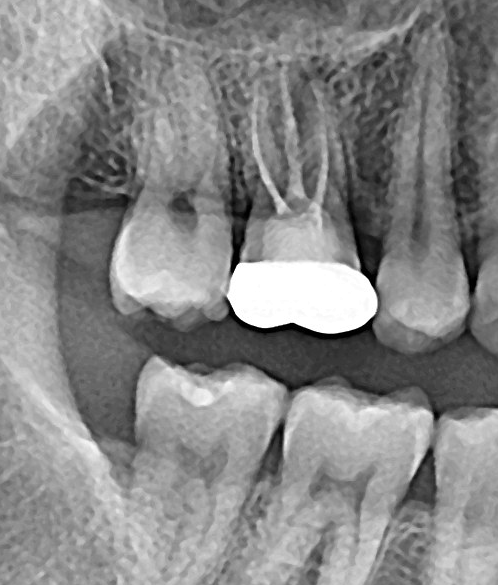

2. 두 치과 모두 뿌리염증이 있다고만 하고 어느 정도인지는 구체적으로 설명을 안 해줬습니다. 사진 상으로 어떤 정도인지 궁금합니다(비교용으로 그간 찍었던 사진을 같이 첨부했습니다) 최근 파노라마를 보면 오른쪽 신경 옆쪽으로 약간 검은 음영이 있는데 이게 뿌리 염증일까요?

그리고 최근 치근단 사진을 보면 신경에서 하얗게 치료된 부분 위로 검은 부분이 보이는데 신경치료가 완전하게 되지 않은 게 맞을까요?

2022년 8월 치근단

23년 6월 파노라마, 치근단

-사진상으로 보면 재신경치료를 하시는것보다는 발치를 해야될 가능성이 높아 보이네요.